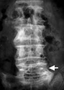

骨密度(骨質疏鬆)檢查

什麼是「骨質疏鬆症」? -